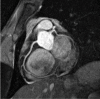

There are advantages to conducting cardiovascular magnetic resonance (CMR) studies at a field strength of 3.0 Telsa, including the increase in bulk magnetization, the increase in frequency separation of off-resonance spins, and the increase in T1 of many tissues. However, there are significant challenges to routinely performing CMR at 3.0 T, including the reduction in main magnetic field homogeneity, the increase in RF power deposition, and the increase in susceptibility-based artifacts.In this review, we outline the underlying physical effects that occur when imaging at higher fields, examine the practical results these effects have on the CMR applications, and examine methods used to compensate for these effects. Specifically, we will review cine imaging, MR coronary angiography, myocardial perfusion imaging, late gadolinium enhancement, and vascular wall imaging.